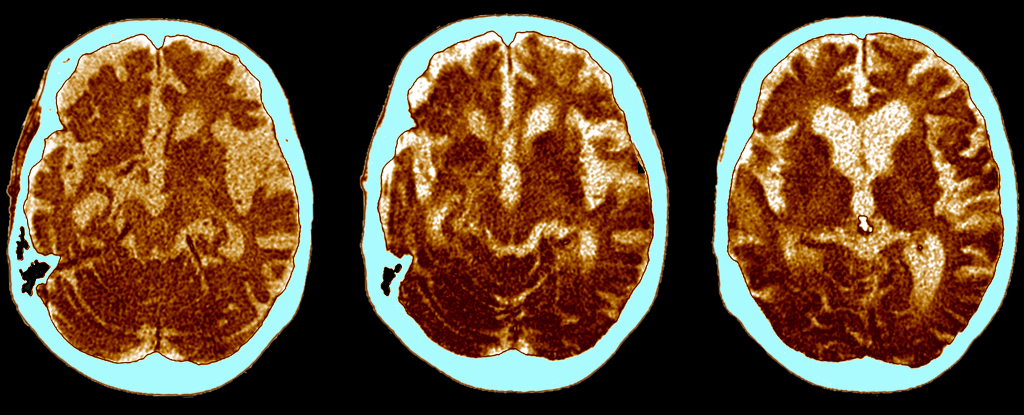

Scientists at the University of Kentucky developed a mouse model that can switch the APOE gene from a high-risk to a protective form in adults, leading to improvements in Alzheimer’s disease markers and cognitive function, highlighting potential gene-based therapies for the future.